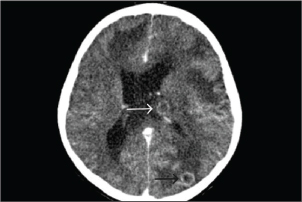

KOH examination of the abscess material demonstrated septate hyphae. Histopathological analysis of the brain abscess from the right frontal lobe revealed uniform, dichotomously branching septate hyphae with acute-angle branching infiltrating the vascular wall and surrounding brain parenchyma (Fig. 2). CSF analysis revealed hypoglycorrhachia, elevated protein, and neutrophilic pleocytosis (Table 1). Cryptococcal antigen testing was negative. There was no radiologic evidence of disseminated aspergillosis involving the lungs or paranasal sinuses. Extensive microbiological investigations for aerobic and anaerobic bacteria, Mycobacterium tuberculosis, Nocardia spp., herpes simplex virus, cytomegalovirus, and Toxoplasma gondii were negative. Serum galactomannan testing showed 0.42; CSF galactomannan and β-D-glucan assays were not performed. These findings supported a diagnosis of multiple cerebral abscesses caused by aspergillosis without evidence of extracranial dissemination.

Fig. 2. Brain abscess, Hematoxylin and eosin (H&E) stain, 40×: on day 23 of admission, Fungal hyphae typically branch at acute angles in the necrotic area (black arrow).